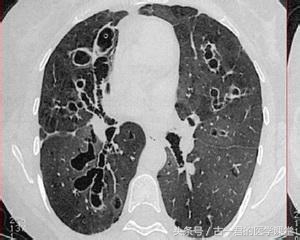

(1)胸部射线检查(为较常用诊断方法,包括胸部X线检查、胸部CT、MRI等):可见肺纹理增粗紊乱,典型表现“蜂窝状”、“卷发状”阴影(正常支气管如同树根,向下越分越细,支气管扩张后向下本应逐渐变细的细支气管扩张,形成上述阴影,如下图)。但因胸部X线检查对中末细支气管观察存在局限,CT为断层扫描,也存在遗漏病变部位的情况,所以引申出了支气管造影检查。

支气管扩张